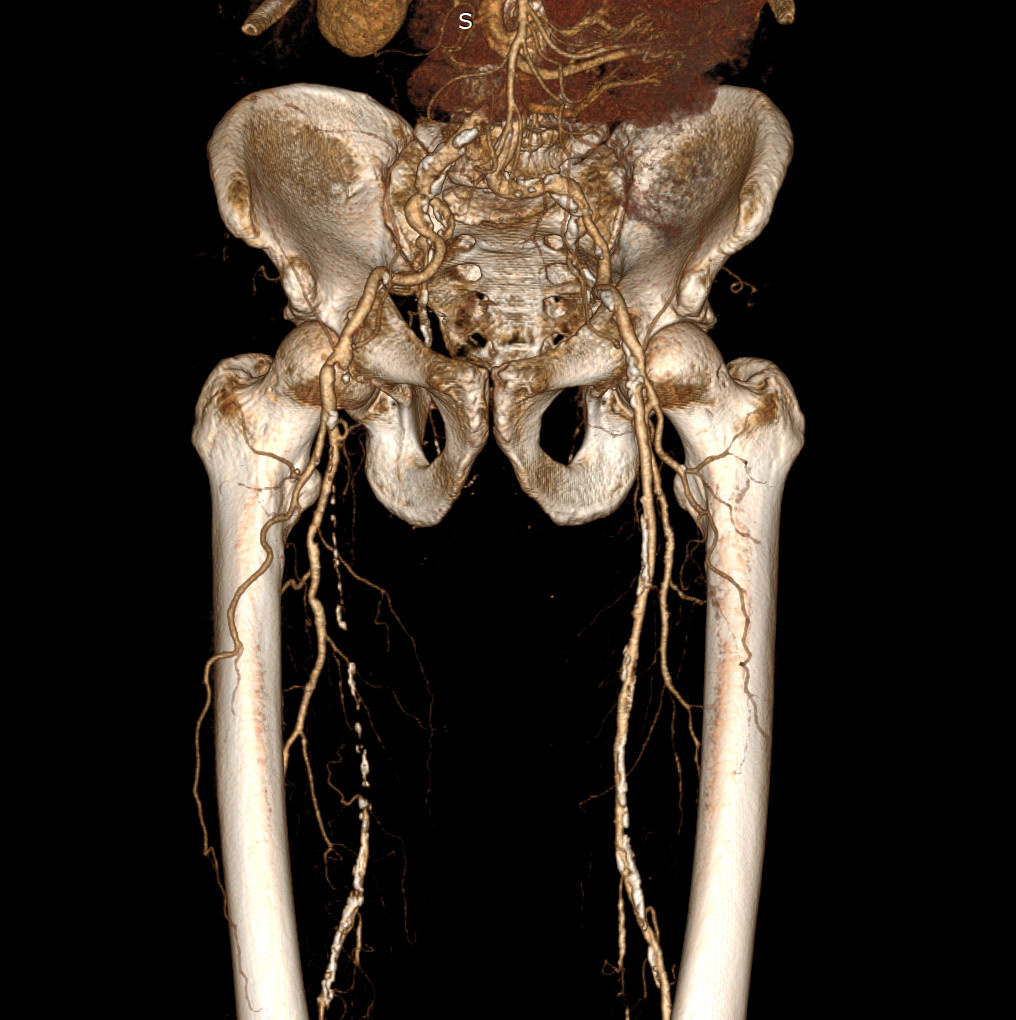

КТ-ангиография артерий нижних конечностей (на фото: 3-х мерная реконструкция сосудистого русла) - наиболее объективный метод исследования артерий нижних конечностей